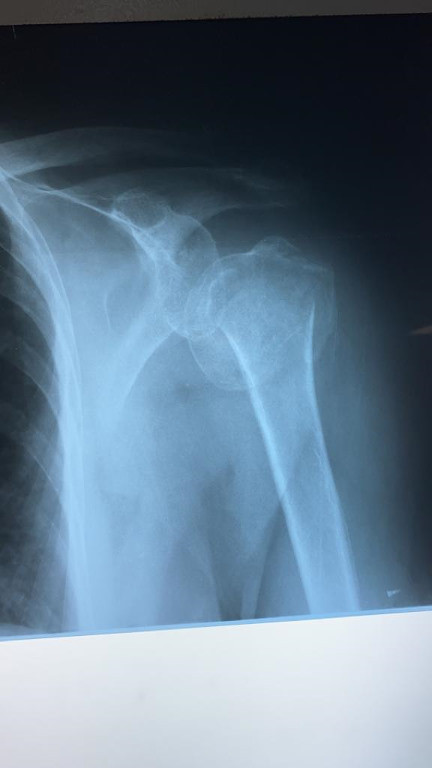

Imágenes de ortopedia y traumatología

Envíado por Dr. José Israel Flores Hernández